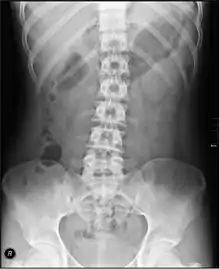

تشكل الأمعاء الغليظة كلا من الأعور، والقولون، والمستقيم، والقناة الشرجية.[11][12] وتوجد بكتريا تعيش في الامعاء الغليظة وهي غير ضارة بالنسبة للإنسان إلا في حالات نقص المناعة المكتسبة (الإيدز) وظيفتها هي أنها تساعد على تخمير بقايا النشويات والبروتين لتسهيل الامتصاص وكذلك امتصاص الماء وبعض الأملاح المعدنية. عند إصابة الأمعاء الغليظة ببعض الأمراض قد يظهر الدم في البراز كأول علامات المرض كما قد يؤدي إلى الإصابة بالإمساك أو قد يسبب المغص وارتفاع درجة حرارة الجسم. الفحوصات التي تؤكد وجود مشكلة ما في الأمعاء الغليظة تشمل إجراء التصوير بالأشعة السينية للبطن أو تنظير القولون.